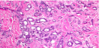

What is this showing?

There is a very pink epithelium characteristic of a nonproliferative cyst. Frequently, the lining cells are large and polygonal with eosinophilic cytoplasm, a process called apocrine metaplasia which is virtually always benign